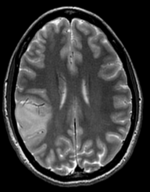

this is the fixed reference image. All images are aligned into this space lleft this is the T2 reference image, serves as target to the DTI baseline, but is itself aligned to the SPGR lleft this is the DTI Baseline scan, to be registered with the T2 this is the DTI tensor image, in the same orientation as the DTI Baseline

Registered DTI superimposed on SPGR and T2 registered (cycles show T1 and T2 and color DTI overlay)